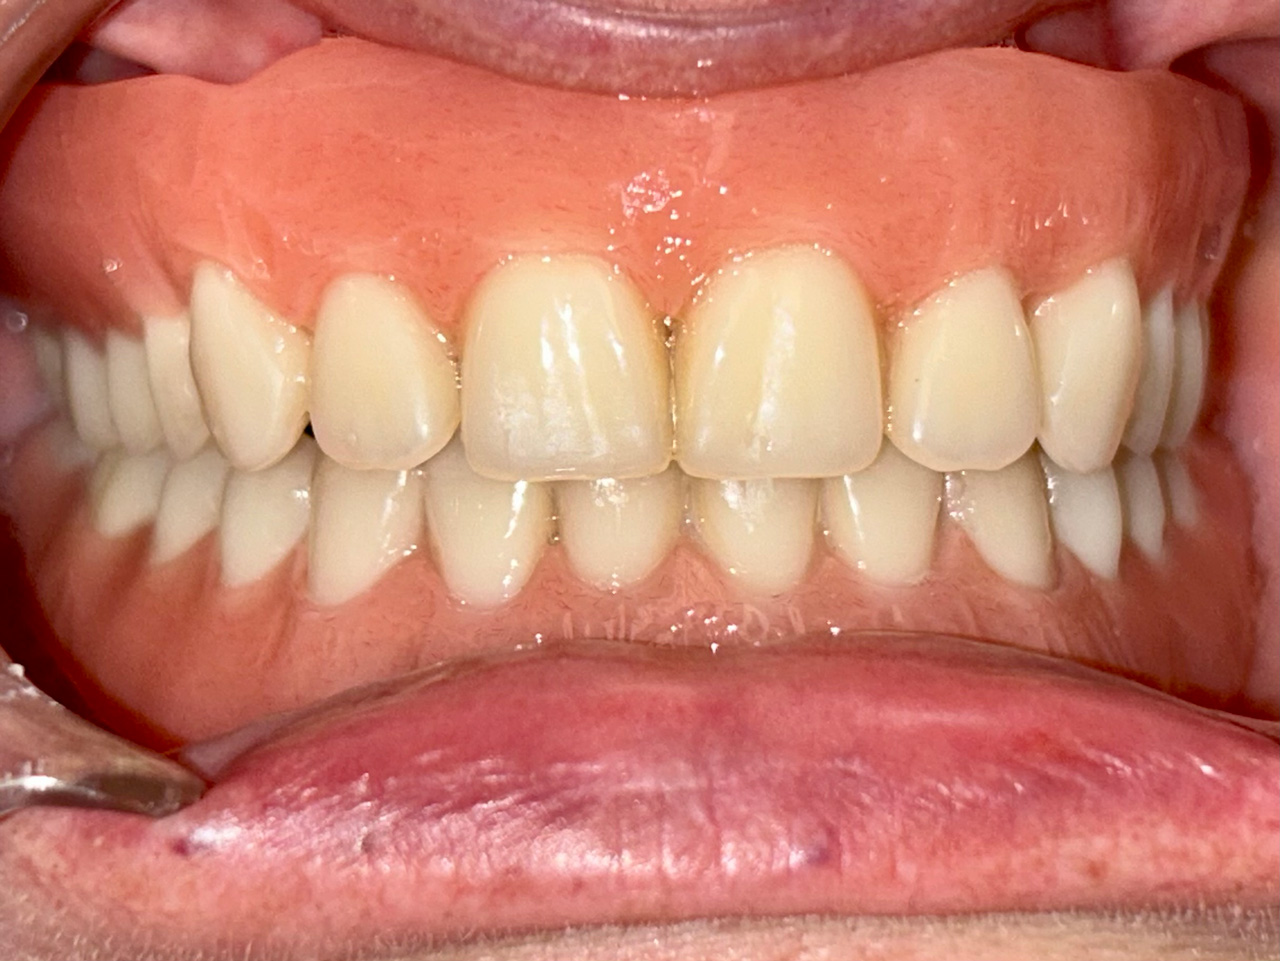

Teljes alsó,felső állcsont helyreállítása azonnal

terhelhető implantátumokkal és porcelán hidakkal.